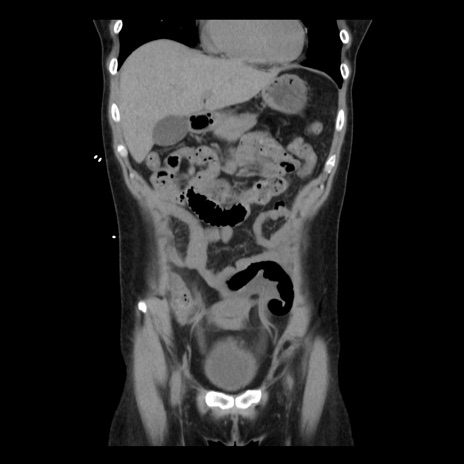

症例10(冠状断像)

【症例】 50歳代女性

【主訴】 腹痛

【現病歴】前日生レバーを食べた。今朝に排便あり。 昼前に突然発症の腹痛を生じ、当院救急外来を受診した。

【既往歴】 子宮筋腫にてで子宮全摘後

【身体所見】 意識清明、腹部:平坦、軟、下腹部やや左を中心に圧痛・反跳痛あり、筋性防御あり

【データ】WBC 7800、CRP 0.07